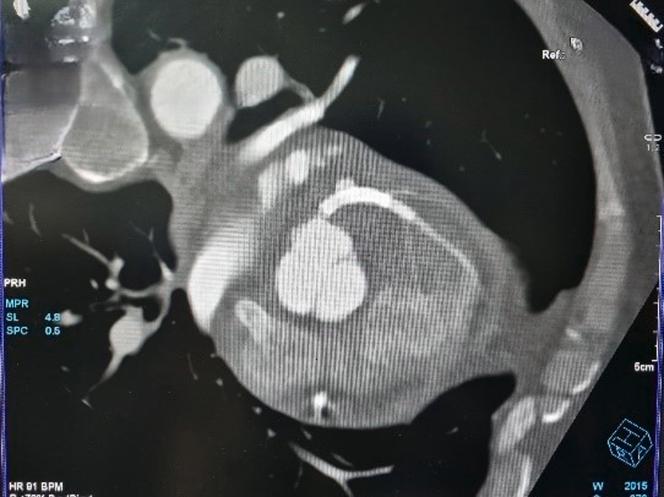

Coronary stent infection is a rare complication with a high mortality rate. We report a case of left anterior descending artery coronary stent infection and pseudoaneurysm that was successfully managed with timely intervention.

A middle-aged man who underwent a recent percutaneous coronary intervention (PCI) presented with fever and ischemic chest pain. Coronary angiography diagnosed coronary stent infection and pseudoaneurysm. The patient underwent successful emergency coronary artery bypass graft surgery with pseudoaneurysm resection and was successfully discharged.

TAKE-HOME MESSAGE: This case highlights that diagnosis of coronary stent infection requires a high degree of suspicion, and multimodality imaging helps in confirmation of diagnosis, early detection of life-threatening complications, and appropriate timely intervention.